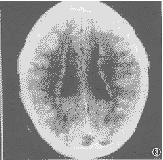

团块状(病灶大于3cm)10处(均为儿童组)(图1),结节状(病灶小于3cm)3处(儿童组1例,成人组2例)(图2),串珠状2处(成人组1例)(图3),环带状2处(儿童组1例)(图4)。

图1 男,1岁4个月。平扫:左额部巨大灰质团块压迫左侧侧脑室,使其变形。

右侧的脑室几乎与中线平行,为胼胝体发育不全表现。同时近中线伴背侧囊肿